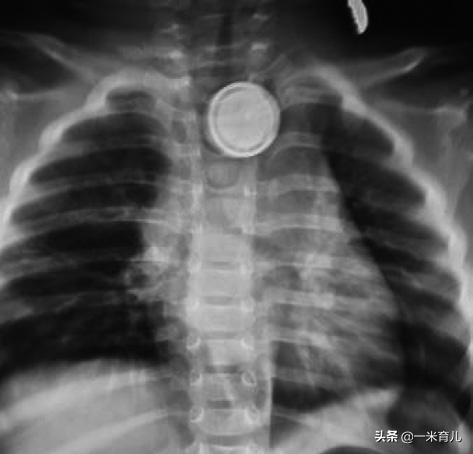

在儿童消化道异物中,70%~75%的消化道异物发生在食管,以食管入口处最多见。

儿童食管异物的表现与成人有所不同,多为哭闹、拒绝饮食、吞咽困难、流涎、呕吐等,有时候孩子也会自述胸痛,部分可表现为呛咳、咳嗽、痰多、呼吸困难等呼吸道症状,如果是锐利的异物或者是腐蚀性异物的话,极有可能引起食道穿孔,而引发食管瘘、出血等意外。

食道异物常见类型分布